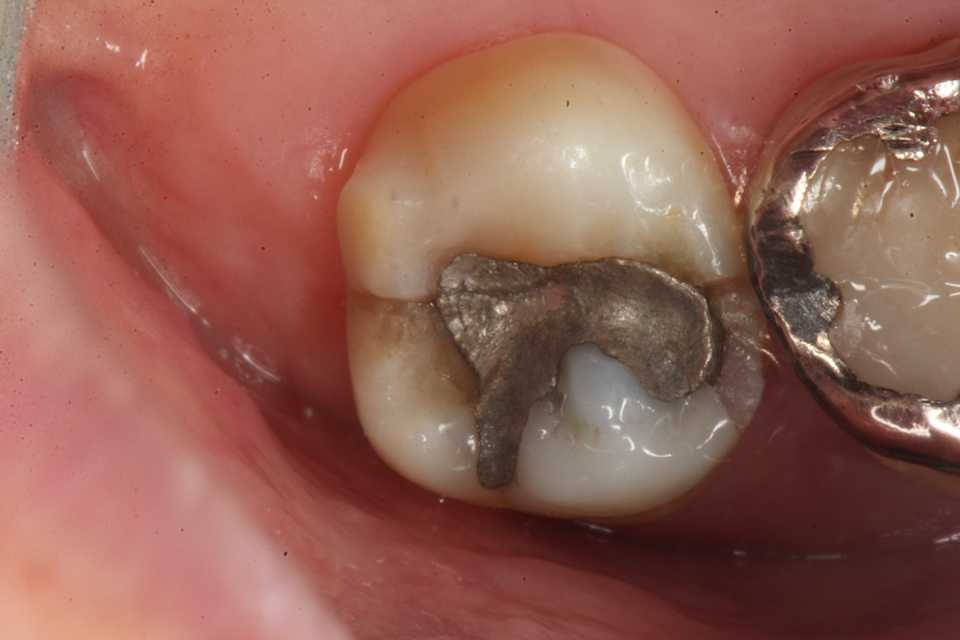

50代女性、左上7、外傷性近心辺縁隆線破折、クラック、自覚症状なし食いしばりの癖がある方で、手前側の6番も補強冠を入れて歯牙破折をなんとか抑えている。この7番も割れて抜歯になる前に補強冠を装着するしかないだろう。とりあえず今日は既存のアマルガムを除去しCRで修復するまで。では時系列でどうぞアマルガムにもクラック(ヒビ)が入っている。クラックα-TCP手前は補強冠、後ろの7番も同じようにするしかないだろう。クラックが深部に進んで離断してしまったら抜歯になる。つづく